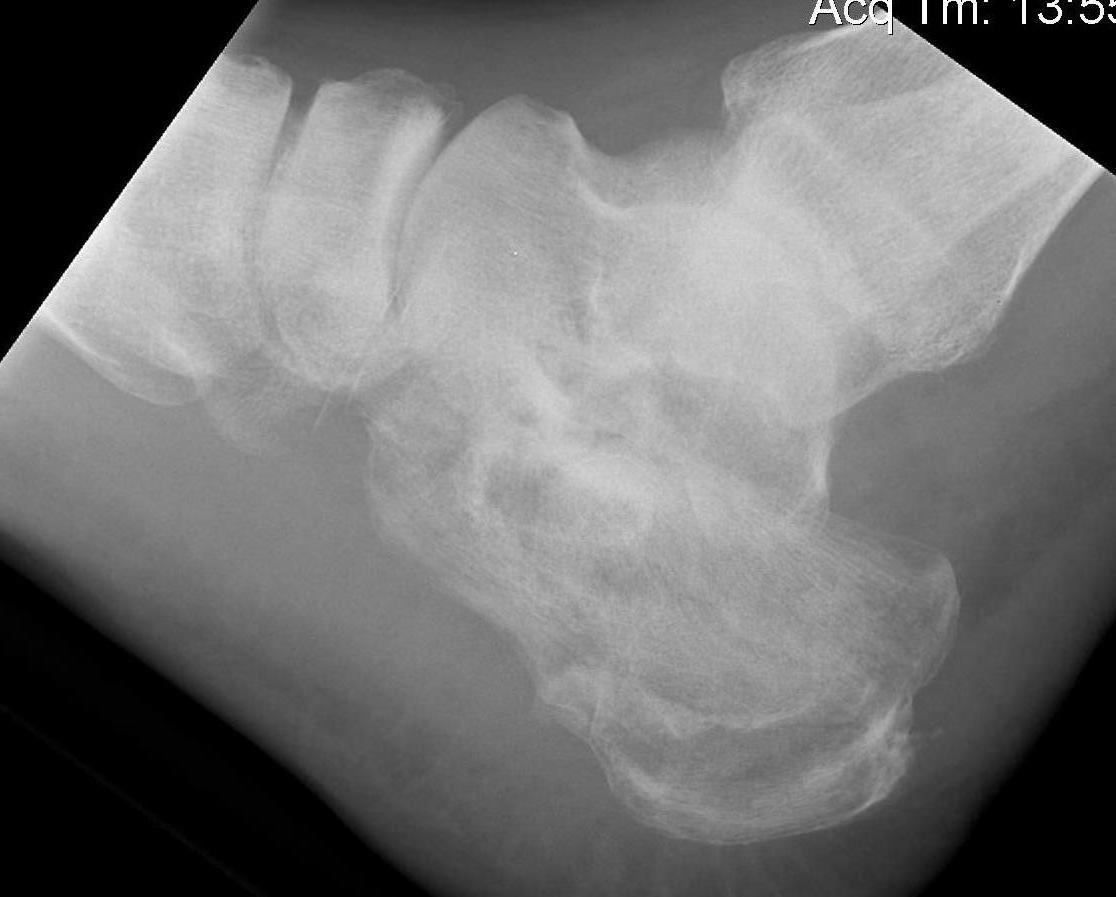

Sander I - non displaced

Sanders IV

Subtalar OA

Calcaneocuboid arthritis

Hindfoot varus malunion

Peroneal impingement or subluxation

Posterior tibial nerve entrapment